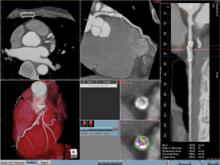

July 15, 2009 - TeraRecon Inc., a developer of imaging processing technology, decision support and 3D visualization solutions, appointed of Dr. TieCheng “TC” Zhao, Ph.D. as vice president of engineering to lead TeraRecon’s engineering team into the next great wave of innovation.